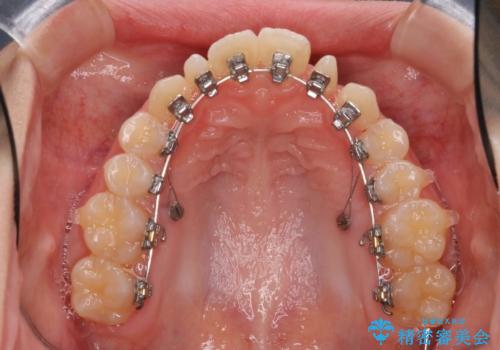

- 矯正装置

- ハーフリンガル

- ハーフリンガルシステムによる矯正治療を行いながら、スペースコントロールをみて前歯を仮歯へ

→矯正の終了をメドに仮歯をセラミックへ置き換える